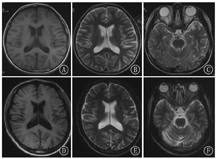

家系1的先证者和父亲均进行4 h的脑电图监测和头颅影像学检查。先证者的脑电图显示广泛性棘波、棘慢波发放及局灶性放电,其父亲显示为偶见额极、额、中央区不典型尖波散发。先证者及其父亲均有脑沟加深和小脑萎缩(图2)。

家系2的先证者、弟弟及父亲进行4 h的脑电图监测,均显示广泛性棘波、棘慢波发放及局灶性放电,先证者的脑电图见图3。先证者进行头颅影像学检查,提示大脑皮质和小脑萎缩。